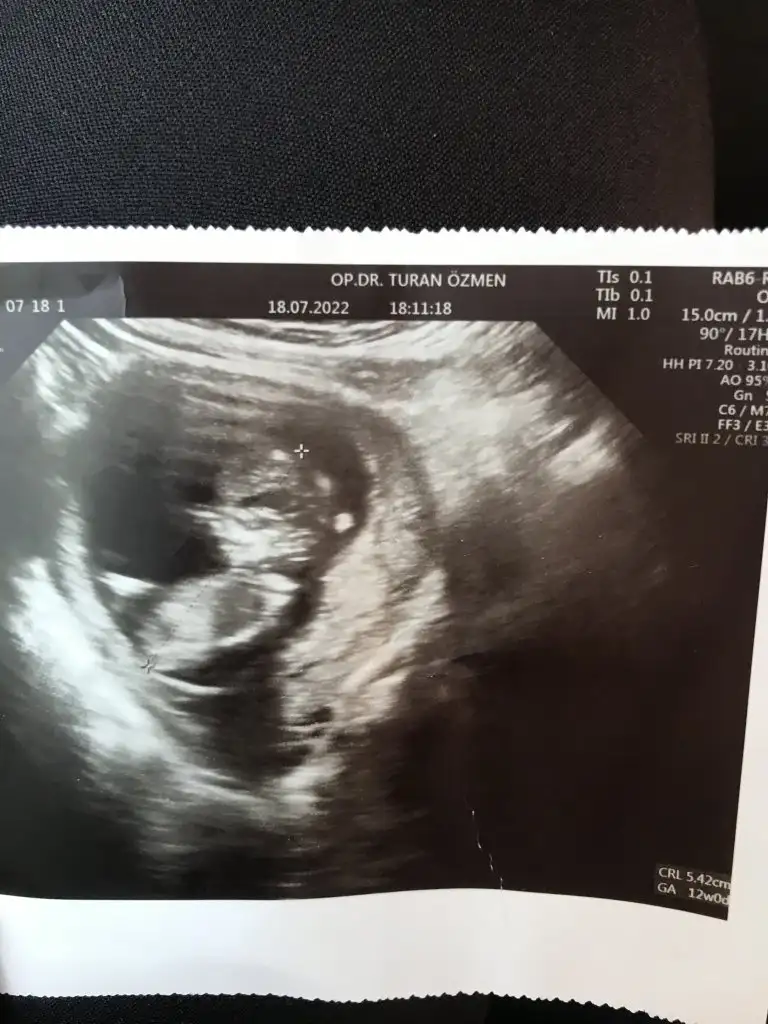

Karından utrason fotosu ayrıca 14 haftalikSelamm ilk görüyorum siziıi

Meraktan çatlıyorum bana da bakar mısınız rica etsem